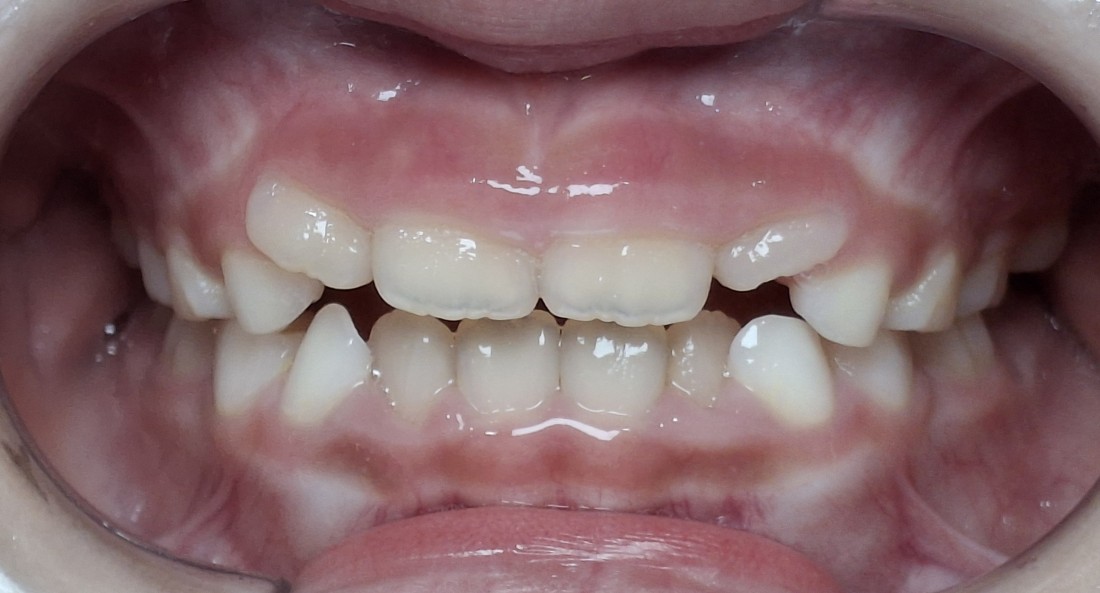

실제로 대한치과교정학회 치료지침 상

어린이 부정교합의 경우

턱 성장과 밀접한 관련이 있기 때문에

혼합치열기 (만5세~12세) 사이에

골든타임을 지켜

조기에 치료를 시작하는 것을

적극적으로 권장합니다.